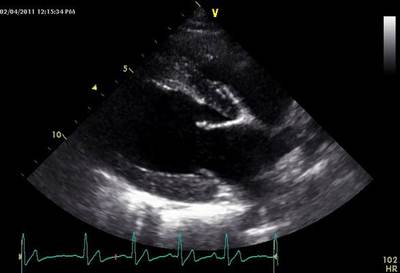

Question

Which image below is of an ECHO on the long axis?